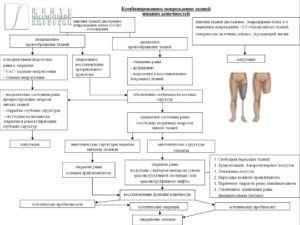

Для успешной пластической реконструкции при раневых дефектах в области нижних конечностей необходим комплексный подход [2], который включает в себя рассмотрение возможности применения соответствующих хирургических методов и критических факторов пациента, которые могут ограничивать применение сложных или длительных операций. Традиционная система приоритетов в отношении методов реконструктивной хирургии подразумевает использование концепции, известной под названием «реконструктивной лестницы» (“reconstructive ladder”) [9,10,11]. Последняя приемлема и для реконструкции нижних конечностей, как первый принцип. Однако, разрабатывая план лечения хирург не должен использовать ее как догму. Предпочтительнее будет выбор методики с учетом функциональности реконструированных тканей в будущем. Для примера: на опорной поверхности стопы, даже когда раневой дефект мог бы быть закрыт более простым методом – кожным аутологичным трансплантатом, предпочтительнее использовать транспозиционный или даже свободный лоскут с хорошо развитой дермой и гиподермой. Несмотря на то, что такой план будет изначально сложнее и риски выше, оправданием может служить цель такой реконструкции, когда планируется замещение дефекта новым покровом, наиболее соответствующим утраченному. В случае успешной реализации это обеспечит значительное улучшение конечного результата и/или сокращение количества этапных вмешательств. Таким образом, вторым принципом можно назвать «реконструктивный лифт» («reconstructive elevator»), который утверждает, что самый простой метод не всегда будет наилучшим выбором [12], а опыт хирурга позволит выбрать наилучший уровень инициально (Рис. 1). Кроме того, еще одним, третьим, принципом является наличие необходимых навыков и предпочтений у хирургической бригады, а также ресурсов для технической реализации хирургического плана и послеоперационной реабилитации [13]. Иными словами, этот принцип утверждает, что наилучшим выбором будет тот метод, которым уверенно владеет ведущий хирург и для реализации плана оперативного лечения есть необходимые возможности.

Рис. 1. Система приоритетов в отношении выбора методов пластики подразумевает поступательный переход от простых методов к сложным методам по принципу «реконструктивной лестницы» или по принципу «реконструктивного лифта».

Рис.2. современный алгоритм реконструкции при комбинированных повреждениях нижних конечностей.